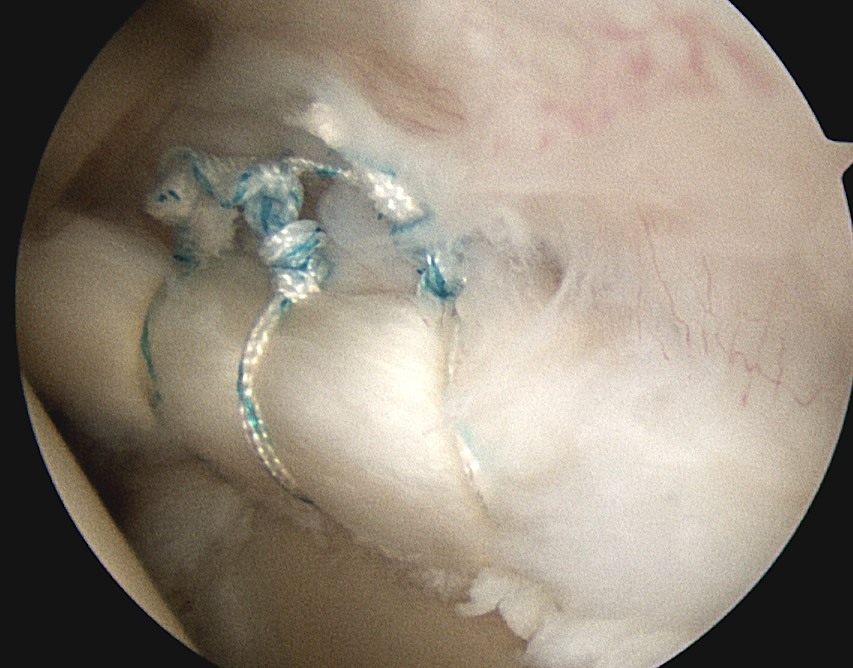

3. Anchors

Usually 3 anchors is a minimum

Technique

- insert anchor

- suture through each cannula

- limb through W portal will be the suture limb that is passed

- retrieve sutures and tie from port of Wilmington

Posterior 2 anchors